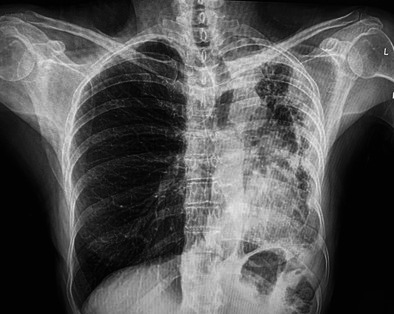

支气管内脂肪瘤是一种罕见的良性肿瘤,起源于支气管壁粘膜下脂肪,占所有肺部肿瘤的不到0.5%。这些肿瘤可表现为非特异性呼吸道症状,通常类似于常见的肺部疾病,如哮喘、慢性阻塞性肺病或感染,这使得诊断具有挑战性。我们提出的情况下,54岁的女性吸烟者谁经历了三个月的历史慢性生产性咳嗽,呼吸困难和反复呼吸道感染。在此期间,她接受了三名医疗服务提供者的评估,根据支气管炎或慢性阻塞性肺病加重的推定诊断,每个人都开了多个疗程的抗生素和吸入支气管扩张剂。值得注意的是,在初始阶段没有进行胸部成像。胸部影像显示左肺萎陷,支气管镜检查显示息肉样肿块阻塞左主支气管。组织病理学分析证实了支气管内脂肪瘤的诊断。本病例强调了在鉴别诊断慢性呼吸系统疾病时考虑良性支气管肿瘤的重要性,特别是在有吸烟史的患者中。完全切除,无论是支气管镜或手术,是治疗的选择,导致良好的预后和症状解决。

Endobronchial lipomas are rare, benign tumours that arise from the submucosal fat of the bronchial wall and account for less than 0.5% of all lung tumours. These tumours can present with non-specific respiratory symptoms, often mimicking common pulmonary conditions such as asthma, COPD, or infections, making diagnosis challenging. We present the case of a 54-year-old female smoker who experienced a three-month history of chronic productive cough, dyspnea and recurrent respiratory infections. During this period, she was evaluated by three healthcare providers, each of whom prescribed multiple courses of antibiotics and inhaled bronchodilators based on presumed diagnoses of bronchitis or COPD exacerbation. Notably, no chest imaging was performed at the initial stages. Chest imaging revealed left lung collapse, and bronchoscopy revealed a polypoidal mass obstructing the left main bronchus. Histopathological analysis confirmed the diagnosis of an endobronchial lipoma. This case highlights the importance of considering benign bronchial tumours in the differential diagnosis of chronic respiratory complaints, especially in patients with a smoking history. Complete excision, either bronchoscopic or surgical, is the treatment of choice, resulting in excellent prognosis and symptom resolution.